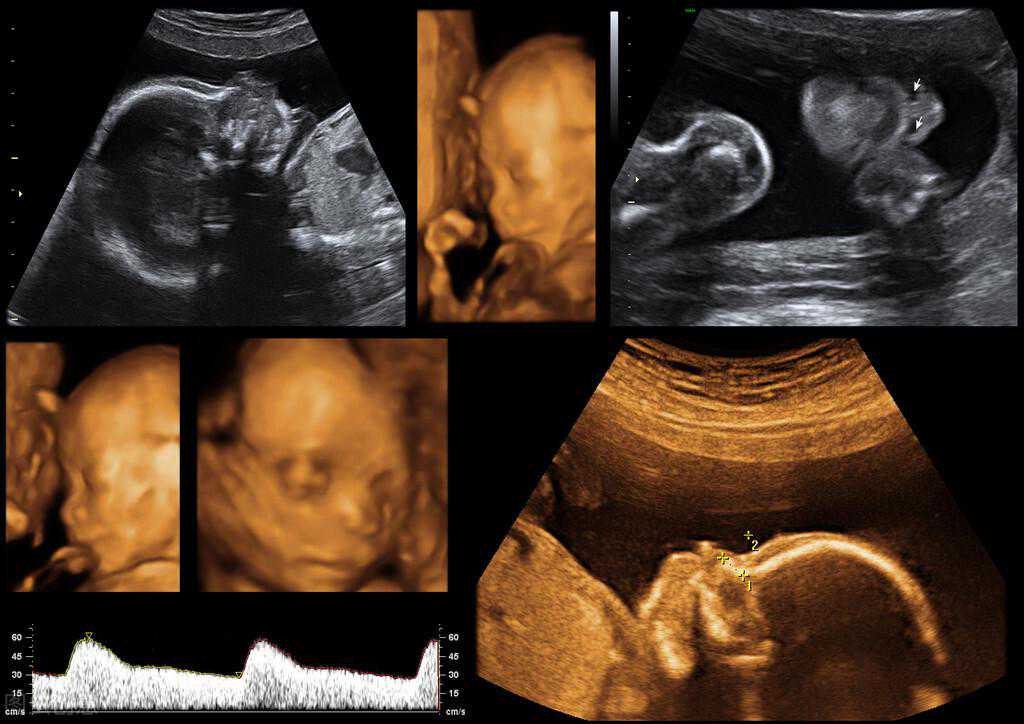

大排畸原理:通过四维彩超,系统筛查胎宝宝有无明显畸形,包括胎儿颜面部,四肢,大脑,以及心脏等畸形。同时还可以通过B超查看宝宝是否生长发育正常等。

大排畸最佳检测时间:孕21~孕24周左右

大排畸其实对应后面还有一次小排畸检查,一般大排畸可以理解为“大器官”排畸,小排畸自然可以理解为“小器官”排畸。因为随着胎儿生长发育,一些小器官也逐渐成熟,可以通过B超进行观察排畸。

大排畸检查最好不要超过孕28周。因为如果过早做这项检查,可能胎儿还比较小,器官相对没有发育好,没办法看清。同时也不要做的太晚,不要超过28周,如果超过这个孕周胎儿长的太大,活动空间会减少,有一次部位及角度可能看不清,不容易观察。

大排畸B超不一定是四维

生活中很多孕妈妈说到四维检查,其实指的是大排畸检查,但我们要知道排畸检查是检查目的命名,而四维是以检查方式命名。

但是,大排畸检查不一定就非得通过四维彩超来做,有些大医院也通过二维B超来做大排畸检查。但通过四维彩超,可以将胎儿的面部以及器官成像,这样更能提供准确的科学依据,同时孕妈妈也可以一睹胎儿的“真容”。